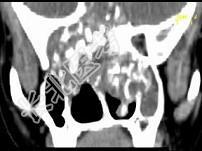

- 单项选择题男,26岁, 进行性鼻腔阻塞、流涕来院就诊,近两年持续性头痛、头晕.如图所示筛窦区占位灶应诊断为 ( )

A、脊索瘤伴左上颌窦炎

B、软骨瘤伴左上颌窦炎

C、骨化性纤维瘤伴左上颌窦炎

D、骨结核伴左上颌窦炎

E、骨纤维异常增殖症伴左上颌窦炎